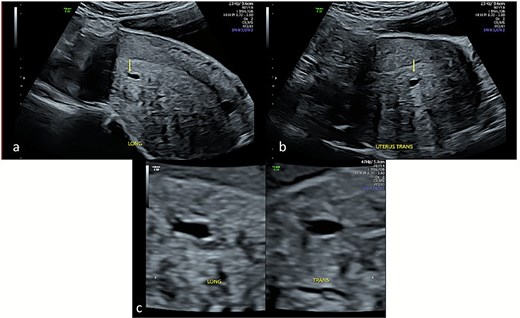

Repeat specialist ultrasound (Fig. 1) identified a right interstitial ectopic pregnancy measuring 27 × 24 × 26 mm, with a decidual reaction, a foetal pole and absent cardiac activity. The gestational sac did not communicate with the endometrial cavity. Diffuse cystic adenomyosis was noted (Fig. 2). Retrospective review indicated that sub-endometrial microcysts had been mistaken for a gestational sac on earlier scans (Fig. 3).

Transvaginal ultrasound of the uterus demonstrating adenomyotic spaces in the myometrium and sub-endometrial border in longitudinal (a) and transverse planes (b), with a notable absence of decidual reaction around the cystic spaces.

Transabdominal ultrasound of the uterus demonstrating cystic sub-endometrial spaces that were mistaken for a gestational sac in earlier ultrasound scans. The sub-endometrial space is demonstrated in longitudinal (a) and transverse planes (b) and under magnification (c) with a notable absence of decidual reaction around the cystic space.

This case demonstrates how adenomyosis can confound early pregnancy imaging, leading to delayed diagnosis of interstitial ectopic pregnancy. Myometrial cysts and sub-endometrial microcysts—common in adenomyosis—may resemble an early gestational sac, particularly in pregnancies of unknown location. Sub-endometrial microcysts are among the strongest ultrasonographic predictors of adenomyosis [8], and the prevalence is higher among women with subfertility [9]. In this case, adenomyosis-related cystic spaces contributed directly to misinterpretation and delayed recognition of the interstitial pregnancy.